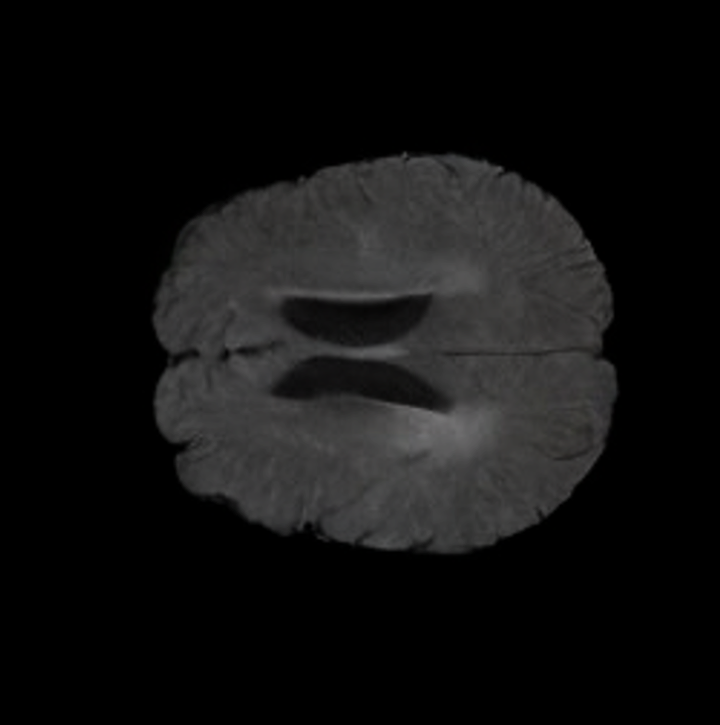

Brain Volumes Preservation. The generated MRIs by our X-Diffusion retain almost the exact same average brain volume vs. of the real MRIs.

Tumour Information Preservation. For the brain tumor segmentation, we use a Swin UNETR model[28, 70], trained with random rotation, and intensity as data augmentation. On the test set with human ground-truth annotations (), the brain volumes generated from single slice input preserve the volume of the different tumour components (paired t-test, for all 3 classes). In Figure 4, we highlight the tumor profiles of the generated MRIs compared to the ground truth tumour profile. The real MRI Dice score in the test set is 85.15 while the generated MRIs from a single slice have a dice score of 83.09. This shows how the generated MRIs indeed preserve the tumor information and can act as an affordable and informative pseudo-MRI, before conducting an actual costly MRI examination in hospitals. More detailed results are provided in supplementary material.

The comparison of generated MRIs versus reference MRIs suggest a nearly perfect preservation of brain volume (in mm3) with median volume of reference MRIs of versus generated MRIs (see an example of brain generation in Figure II).

B.3 Tumour Information Preservation

On the test set with human ground-truth annotations (), the brain volumes generated from single slice input preserve the volume of the different tumour components (paired t-test, for all 3 classes) (see Table I). The real MRI Dice scores are put for reference to our generated MRIs. X-Diffusion outperforms baselines TPDM [39] and ScoreMRI [19] in tumour preservation (see Table I and Figure III). We ran experiments comparing the tumour segmentation Dice Score varying X-Diffusion configurations. The multi-slice input X-Diffusion achieves marginally better Dice Score than the single slice input model (83.47 83.09). We also ran experiments with slice input used for volume reconstruction intersecting or not with tumour. We observe on average a drop of 6% Dice Score (see Table I). Further away from the tumour the input slice for volume reconstruction is selected, we observe a linear decrease in tumour segmentation Dice Score with lowest value of 77.21 Dice Score (see Figure VI).